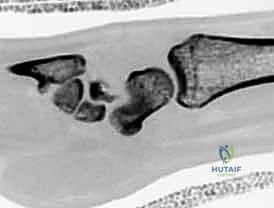

* التصوير بالرنين المغناطيسي (MRI): هو المعيار الذهبي لاكتشاف الكسور المخفية وتقييم التروية الدموية للقطب القريب.

* الأشعة المقطعية (CT Scan): تستخدم لتحديد شكل الكسر بدقة ثلاثية الأبعاد والتخطيط للعملية الجراحية.